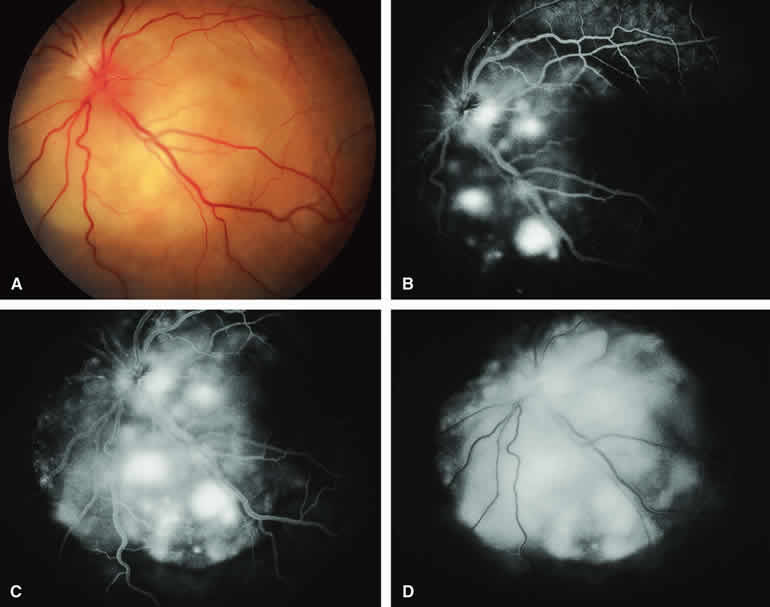

CIRCUMSCRIBED CHOROIDAL HEMANGIOMA

The circumscribed choroidal hemangioma is a benign neoplasm versus hamartoma composed of mature choroidal vascular channels. Fluorescein and ICG angiographic features of these tumors have been described by multiple authors.21,22 The typical circumscribed choroidal hemangioma (Figs. 21A and 22A) is a reddish orange, extremely ill-defined, posterior choroidal tumor that is 5 mm or less in basal diameter and 2 to 3 mm or less in thickness. The overlying retina commonly appears cystic by fundus biomicroscopy, and the retina is often noted to be shallowly detached overlying and surrounding the mass. The posterior margin of virtually all circumscribed choroidal hemangiomas is located within two disc diameters from the optic disc or foveola or both.

Fluorescein angiography of a typical circumscribed choroidal hemangioma (see Fig. 21B, C, and D) shows prominent fluorescence of multiple large-caliber intralesional vessels concurrent with or even before the earliest filling of the normal choroidal and retinal blood vessels. By the late retinal arterial phase frames, the entire lesion is usually diffusely and intensely hyperfluorescent without identifiable distinct intralesional vessels. Fluorescein leaks through the characteristically degenerated overlying retina pigment epithelium into the subretinal space and commonly stains the subretinal fluid and retina diffusely in the late-phase frames.

ICG angiography of a typical circumscribed choroidal hemangioma (see Fig. 22B, C, and D) reveals rapid filling of large-caliber intralesional blood vessels, early intense fluorescence of the vascular tumor, persistent hyperfluorescence of the tumor for 10 to 15 minutes or longer, and late washout of central fluorescence with residual marginal fluorescence by the 20- to 30-minute postinjection frames. This ICG angiographic pattern appears to be almost pathognomonic of circumscribed choroidal hemangiomas and is, therefore, of substantial differential diagnostic value. ICG angiography usually reveals the full extent of the base of the tumor much better and more completely than does fluorescein angiography.